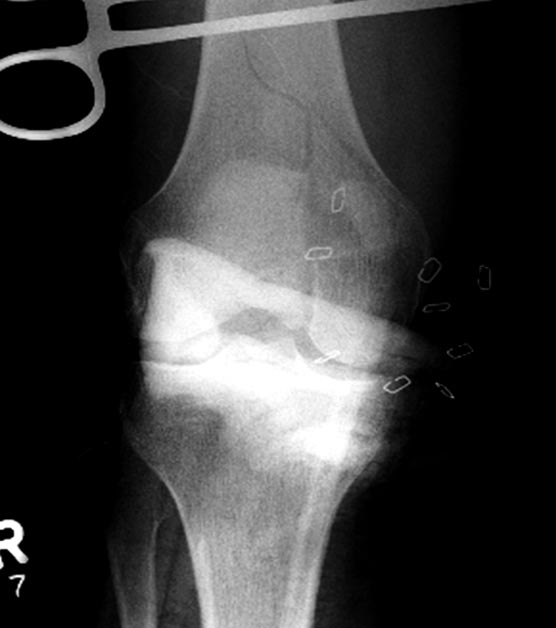

Здесь перечислены ортопедические повреждения: Rt. femoral shaft fracture, Rt femoral head fracture-dislocation, Rt distal femur fracture, Rt. open patella fracture, Rt. talus fracture dislocation, Rt. open humerus fracture, Left 5th metatarsal fracture, Left dislocation 1st TMT.

Фиксировать одним интрамедулярным гвоздем несколько переломов неплохая идея, но это не всегда удается. Для репозиции перелома шейки с вывихом головки (кстати, часть головки до сих пор остается внутри суставной впадины), потребуется много времени. Здесь каждый перелом требует особого подхода: например, для сохранения сферичности головки потребуется обширный доступ, а для остальных переломов различные трюки, что затрудняет фиксацию одним имплантатом!

На 9й день фиксация дистального бедра, где фрагмент Hoffa и вертикальный перелом надколенника, зафиксированы винтами.

На 25 день с момента травмы операция на Jackson table с боковым обширным доступом. Удаление стержней с местной обработкой. В тазобедренном суставе удаление головки, на дне вертлужной впадины полная отслойка хряща. Вертлужный компонент с одним винтом и короткая ножка - Fitmore press fit stem. На второй день однократно доза радиации для профилактики гетеретопической оссификации. Послеоперационный период без температуры. Выписана. Нагрузку разрешили на левой стороне, а полная в 3 мес. Здесь снимки при амбулаторном наблюдении: послеоперационно, 2 мес, 3 мес и 6 мес. Нагрузка полная, отсутствует хромота, и нет жалоб.